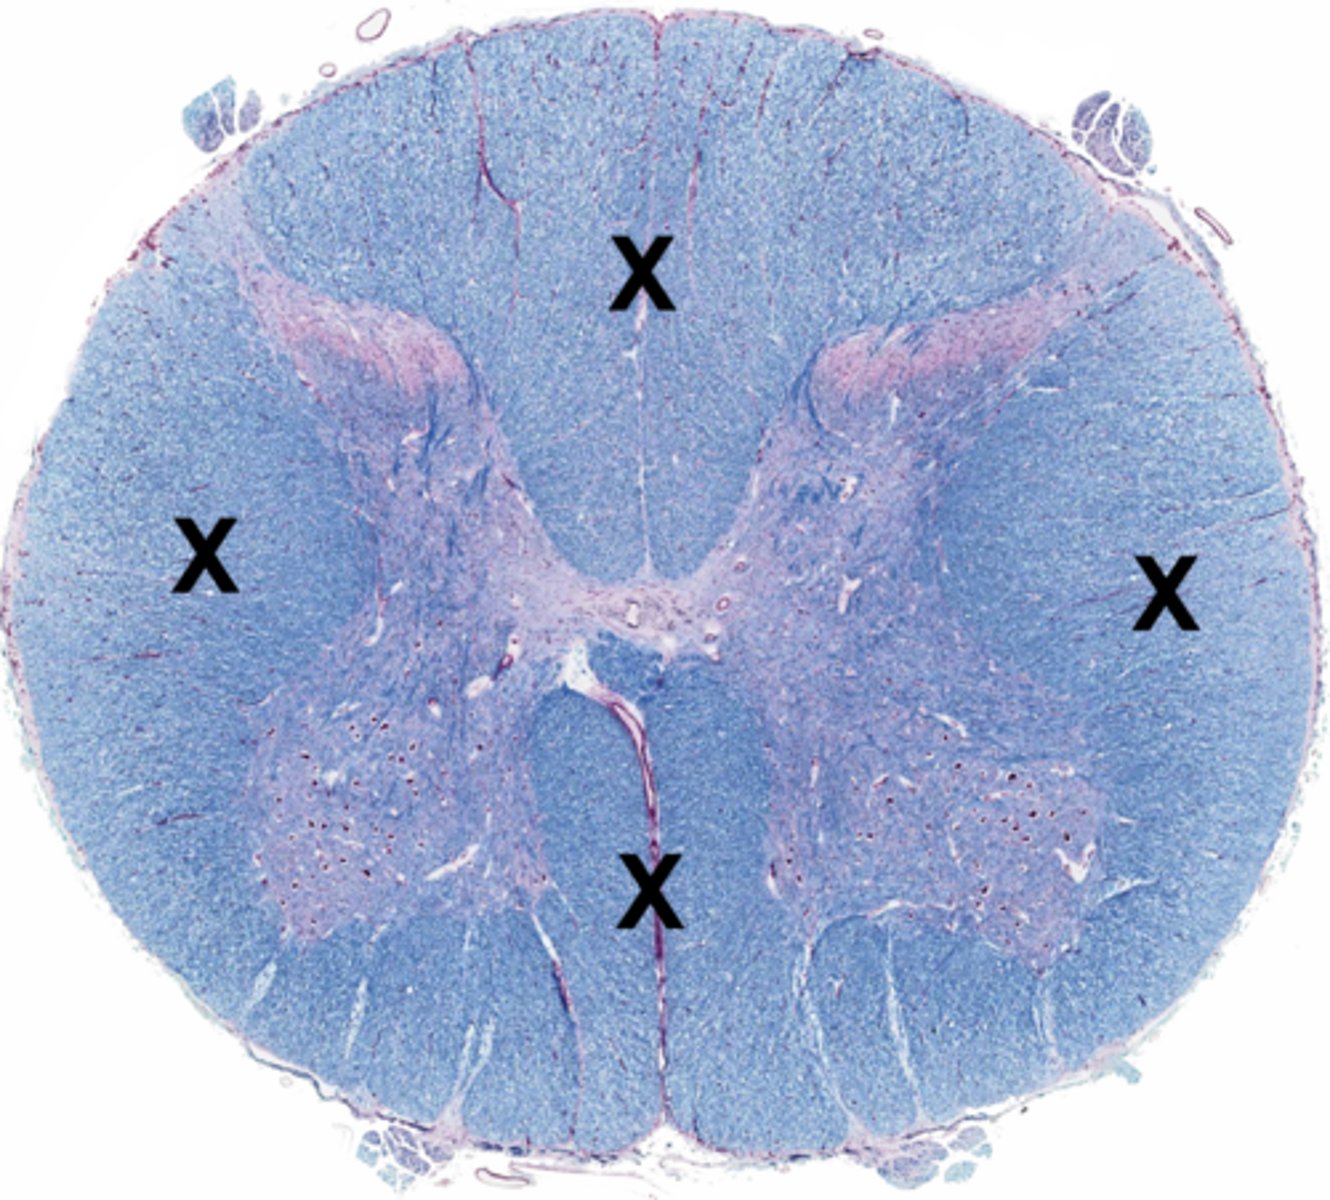

Gray matter

Posterior horn

Anterior horn

Lateral horn

White matter

Posterior funiculus

Anterior funiculus

Lateral funiculus